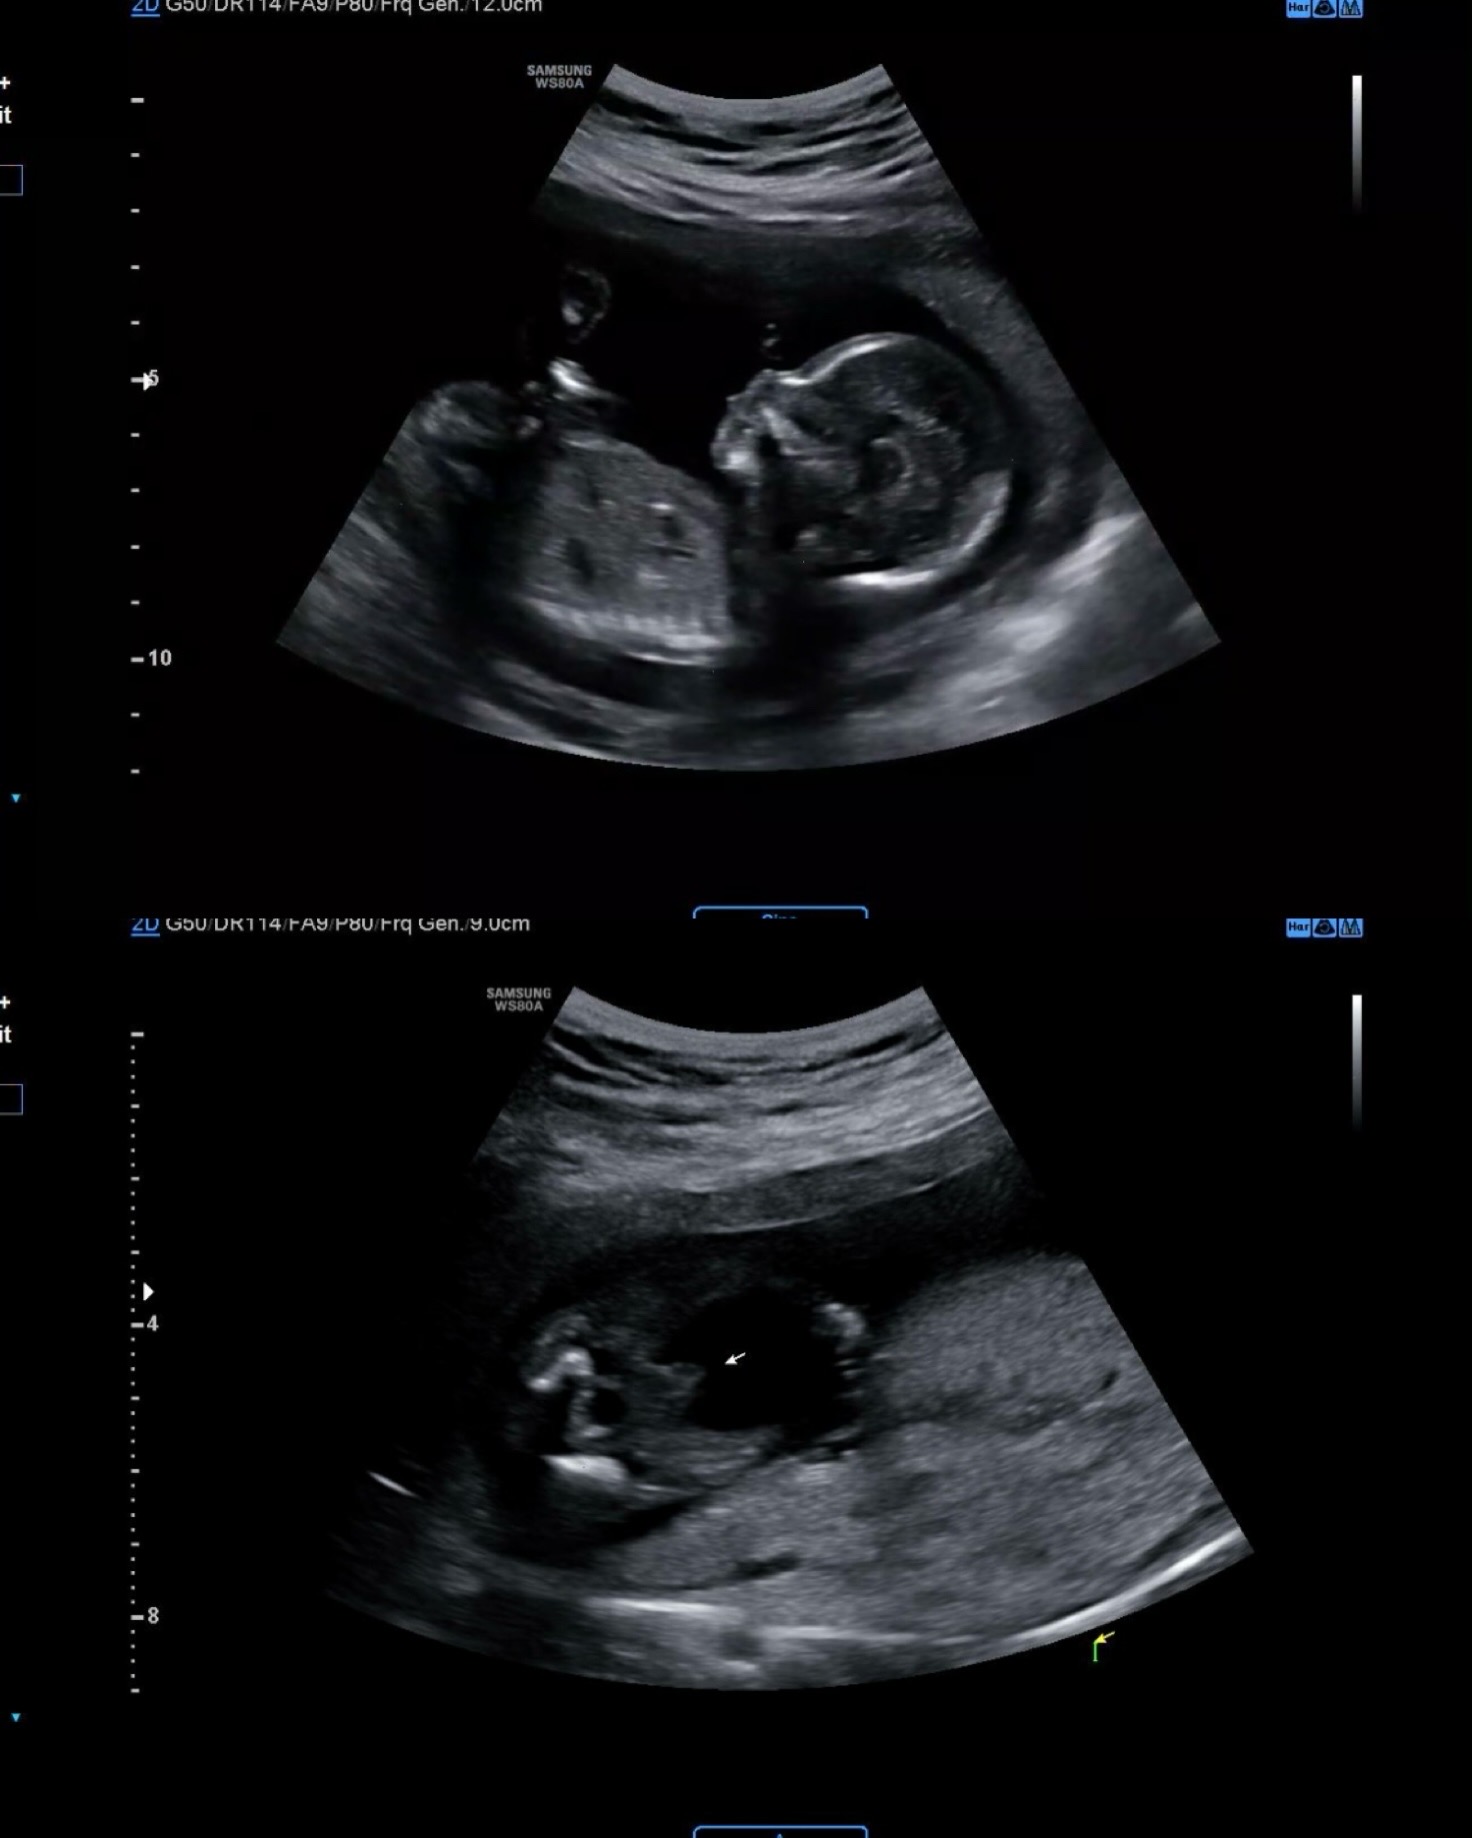

성별 확정 ㅎㅎ

어제 병원가서 성별 확인하고왔어요! 첫째가 딸이라 아들 원했는데 아들 확정 받았어요💙 남매맘 당첨입니당ㅎㅎ 빌리테스트도 75% 아들이었어요